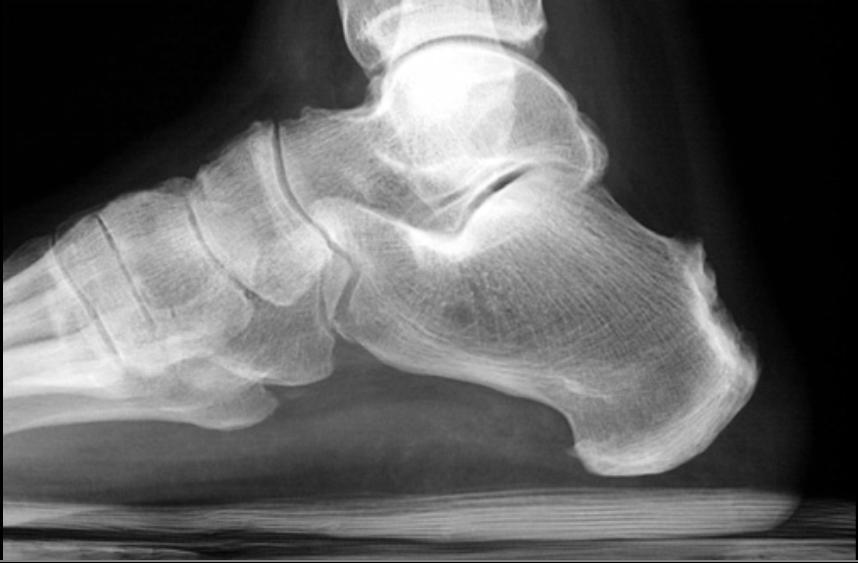

Inflammatory Arthritide: - Males 20-30 yo +/- - Urethritis - Conjunctivitis - Arthritis - Caused by Chlamydia - Calcaneal spur - Fluffy periostitis - Non-marginal syndesmophytes in spine

“Can’t see, Can’t pee, Can’t dance with me”

Reiter’s aka Reactive Arthritis